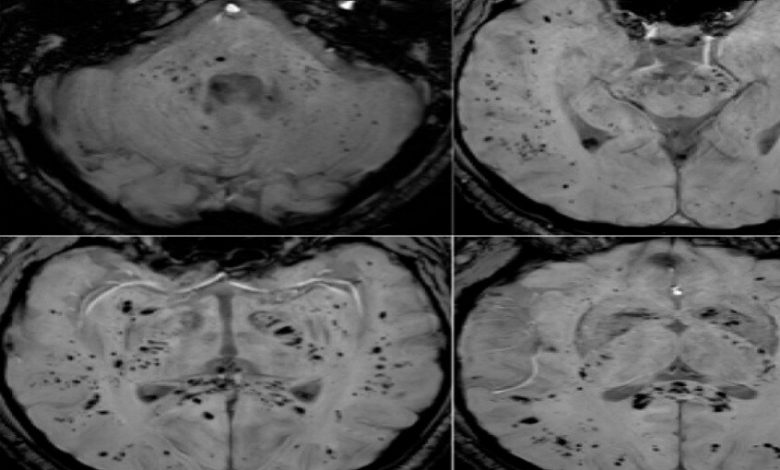

تحليل بالرنين المغناطيسي يكشف تأثير كوفيد-19 المستمر على الدماغ

أظهر تحليل صور بالرنين المغناطيسي أن فيروس كوفيد-19 يترك أثرا لا يُمحى في الدماغ، ويستمر تأثيره حتى بعد التعافي التام.

أظهرت دراسة حديثة أجراها علماء في جامعة غريفيث الأسترالية ونُشرت في مجلة Brain, Behavior, & Immunity Health أن فيروس كوفيد-19 لا يؤثر على الجهاز التنفسي فحسب، بل يترك أثرا ملموسا على الدماغ، ويستمر تأثيره حتى لدى الأشخاص الذين يعتبرون أنفسهم متعافين تماما، حتى إذا لم تظهر عليهم أعراض واضحة.

وأوضح الباحث الرئيسي الدكتور كيران تاباليا أن الفريق استخدم طرق التصوير بالرنين المغناطيسي متعددة الوسائط لدراسة المادة الرمادية والبيضاء في الدماغ، وهي مهمة للذاكرة والوظائف الإدراكية والصحة العامة للدماغ. ووجد الباحثون اختلافات ملحوظة في أنسجة الدماغ وموادها الكيميائية العصبية وشدة الإشارة وبنية الأنسجة لدى المتعافين من كوفيد-19، حتى في حالات الإصابة التي اعتبرت بسيطة.

وأضاف تاباليا: “تبين أن التغيرات في أنسجة الدماغ مرتبطة بشدة الأعراض”، ما قد يفسر مشكلات إدراكية طويلة الأمد مثل تدهور الذاكرة والتركيز، والتي قد تستمر لشهور أو حتى سنوات بعد الإصابة.